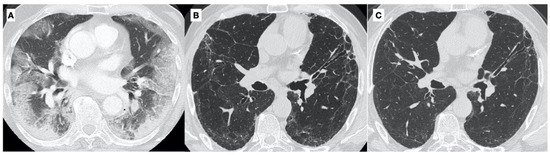

6. Clinical Cases